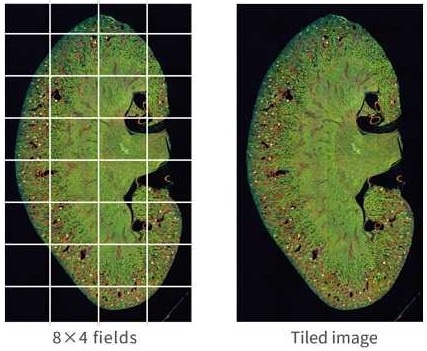

Image stitching

Image Credit: Yokogawa Life Science

Image-stitching generates tiled images, which are then examined to enable reliable quantification. Spheroids, tissue slices, and neurites are all excellent candidates for cross-disciplinary analyses.